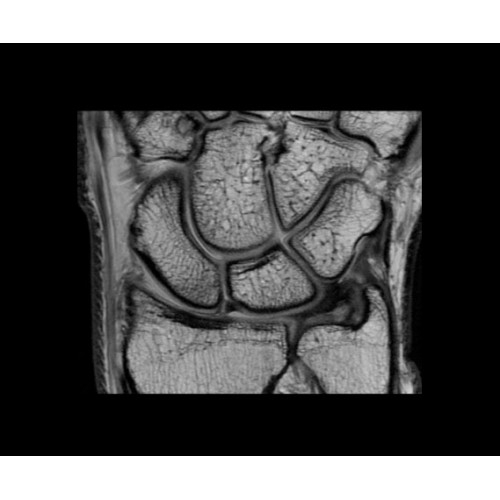

SIGNA PET/MR 3.0T — это гибридная система, в которой совмещаются две принципиально разные технологии — магнитно-резонансную томографию (МРТ) и позитронно-эмиссионную томографию (ПЭТ). Система отличающийся высокой чувствительностью и эффективностью и предназначена для диагностики в области онкологии, неврологии, кардио-васкулярных исследований, исследований воспалительных процессов.

Компания GE Healthcare представляет революционную, полностью интегрированную систему SIGNA PET/MR1, в которой сочетаются времяпролетная технология (TOF) и возможности напряженности магнитного поля 3.0 Тл. Мы поможем вам поднять исследования на более высокий уровень. SIGNA PET/MR позволяет достичь впечатляющей точности и скорости исследований, а благодаря новейшей технологии реконструкции Q.Clear2 качество изображений улучшается в два раза. Кроме того, в систему включен полный набор клинических приложений и гибких катушек для проведения любых видов исследования, открывая для вас возможности визуализации, о которых вы даже не догадывались.

Кроме того, в результате использования технологии TOF и инновационной технологии реконструкции Q.Clear вы сможете добиться прекрасного соотношения сигнал/шум. А благодаря технологии нулевого времени эхо (ZTE) визуализировать костную структуру без ионизирующего излучения. Все эти разработки для улучшения качества сканирования и точности анализа помогут вам использовать весь потенциал ПЭТ/МРТ.

Впечатляющие клинические возможности

Система SIGNA PET/MR предлагает впечатляющие клинические возможности и открывает доступ к наиболее полным пакетам программных приложений.

• МРТ с функцией нулевого времени эхо (ZTE) отличается точностью, возможностью персональных настроек и отсутствием ионизирующего излучения. Она приходит на смену традиционному исследованию на основе рентгеновского излучения. МРТ с функцией нулевого времени эхо (ZTE) на базе SIGNA ПЭТ/МРТ является более надежной и быстрой по сравнению с системами, использующими сверхмалое время эхо (UTE).